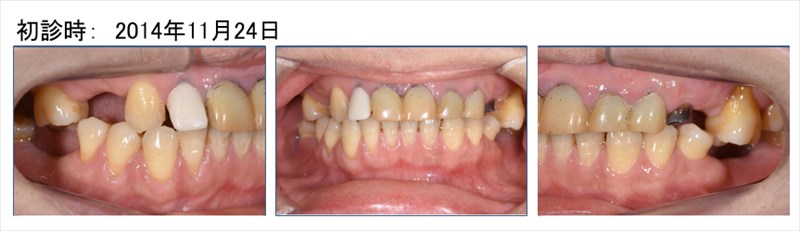

この症例は前歯の揺れを主訴に来た患者さま

奥歯もなく咬めないとおっしゃっていました。

術前のレントゲンでは根尖病変(根の先に膿が溜まっている状態)が確認され、そこに垂直的な骨欠損があり7mmのポケットがありました。右のレントゲンを見て頂くと骨が再生しポケットは2mmに。根尖病変(根の先に膿が溜まっている状態)も改善されています。この症例は歯周病の再生療法と精密根管治療どちらのクオリティーが落ちても上手くいかない症例です。

勿論全体的に歯周病や虫歯も治り良く食べられるとおっしゃって頂けました。